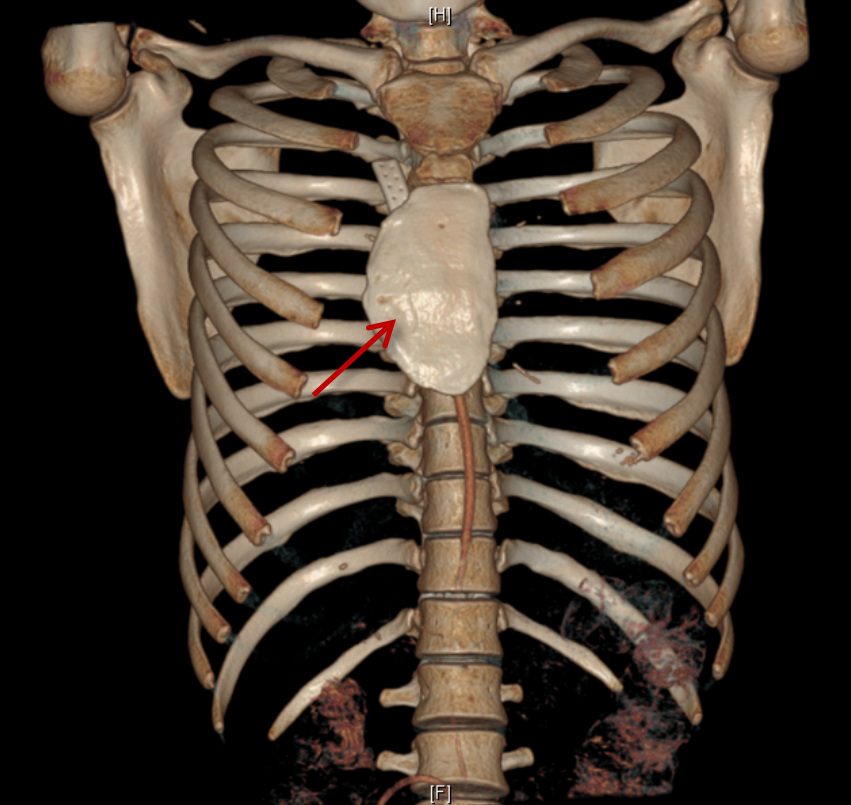

结合CT影像3D重建图像及以往该类手术的临床经验,陈东红组织全科进行多次病例讨论后,为手术准备充分的风险应对预案。手术按两大步骤有序执行——胸骨肿物切除,为了尽可能地清除肿瘤,术中将肿瘤附近的皮肤、皮下组织、距离肿瘤3cm以内的胸肌和肋软骨连同肿瘤整块切除,送检冰冻病理报告切缘阴性;经术中实际探查,肿瘤还没有侵及胸骨后筋膜及胸膜,经过精细的分离,保留了胸膜腔的密闭性,这为手术的第二步打下了好基础,在进行胸壁缺损修复时,采用了聚四氟乙烯(Poly tetra fluoroethylene,PTFE)包被骨水泥成形,对胸廓进行了重建,这一方法在保证胸廓完整性的基础上,满足了足够的胸廓移动度。

为了尽可能缩小刀口,胸外科在术中会诊整形外科医师为小林进行手术切口设计及美容缝合。术后的刀口愈合很快,CT重建胸廓良好,小林一周后便顺利出院了。